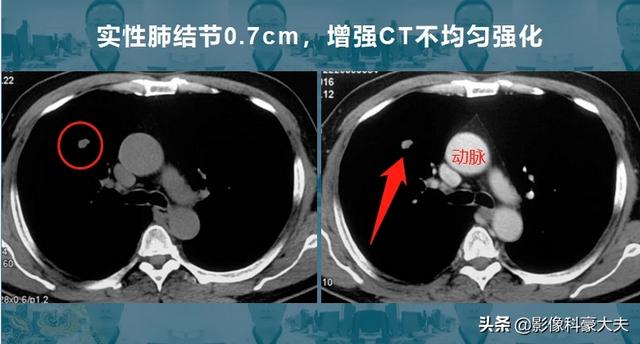

7mmの固形肺結節(山東癌病院の黄教授が共有する症例)で、不規則で、強化CTでは不均一な増強があり、外科病理では転移のない浸潤性肺腺癌であった。